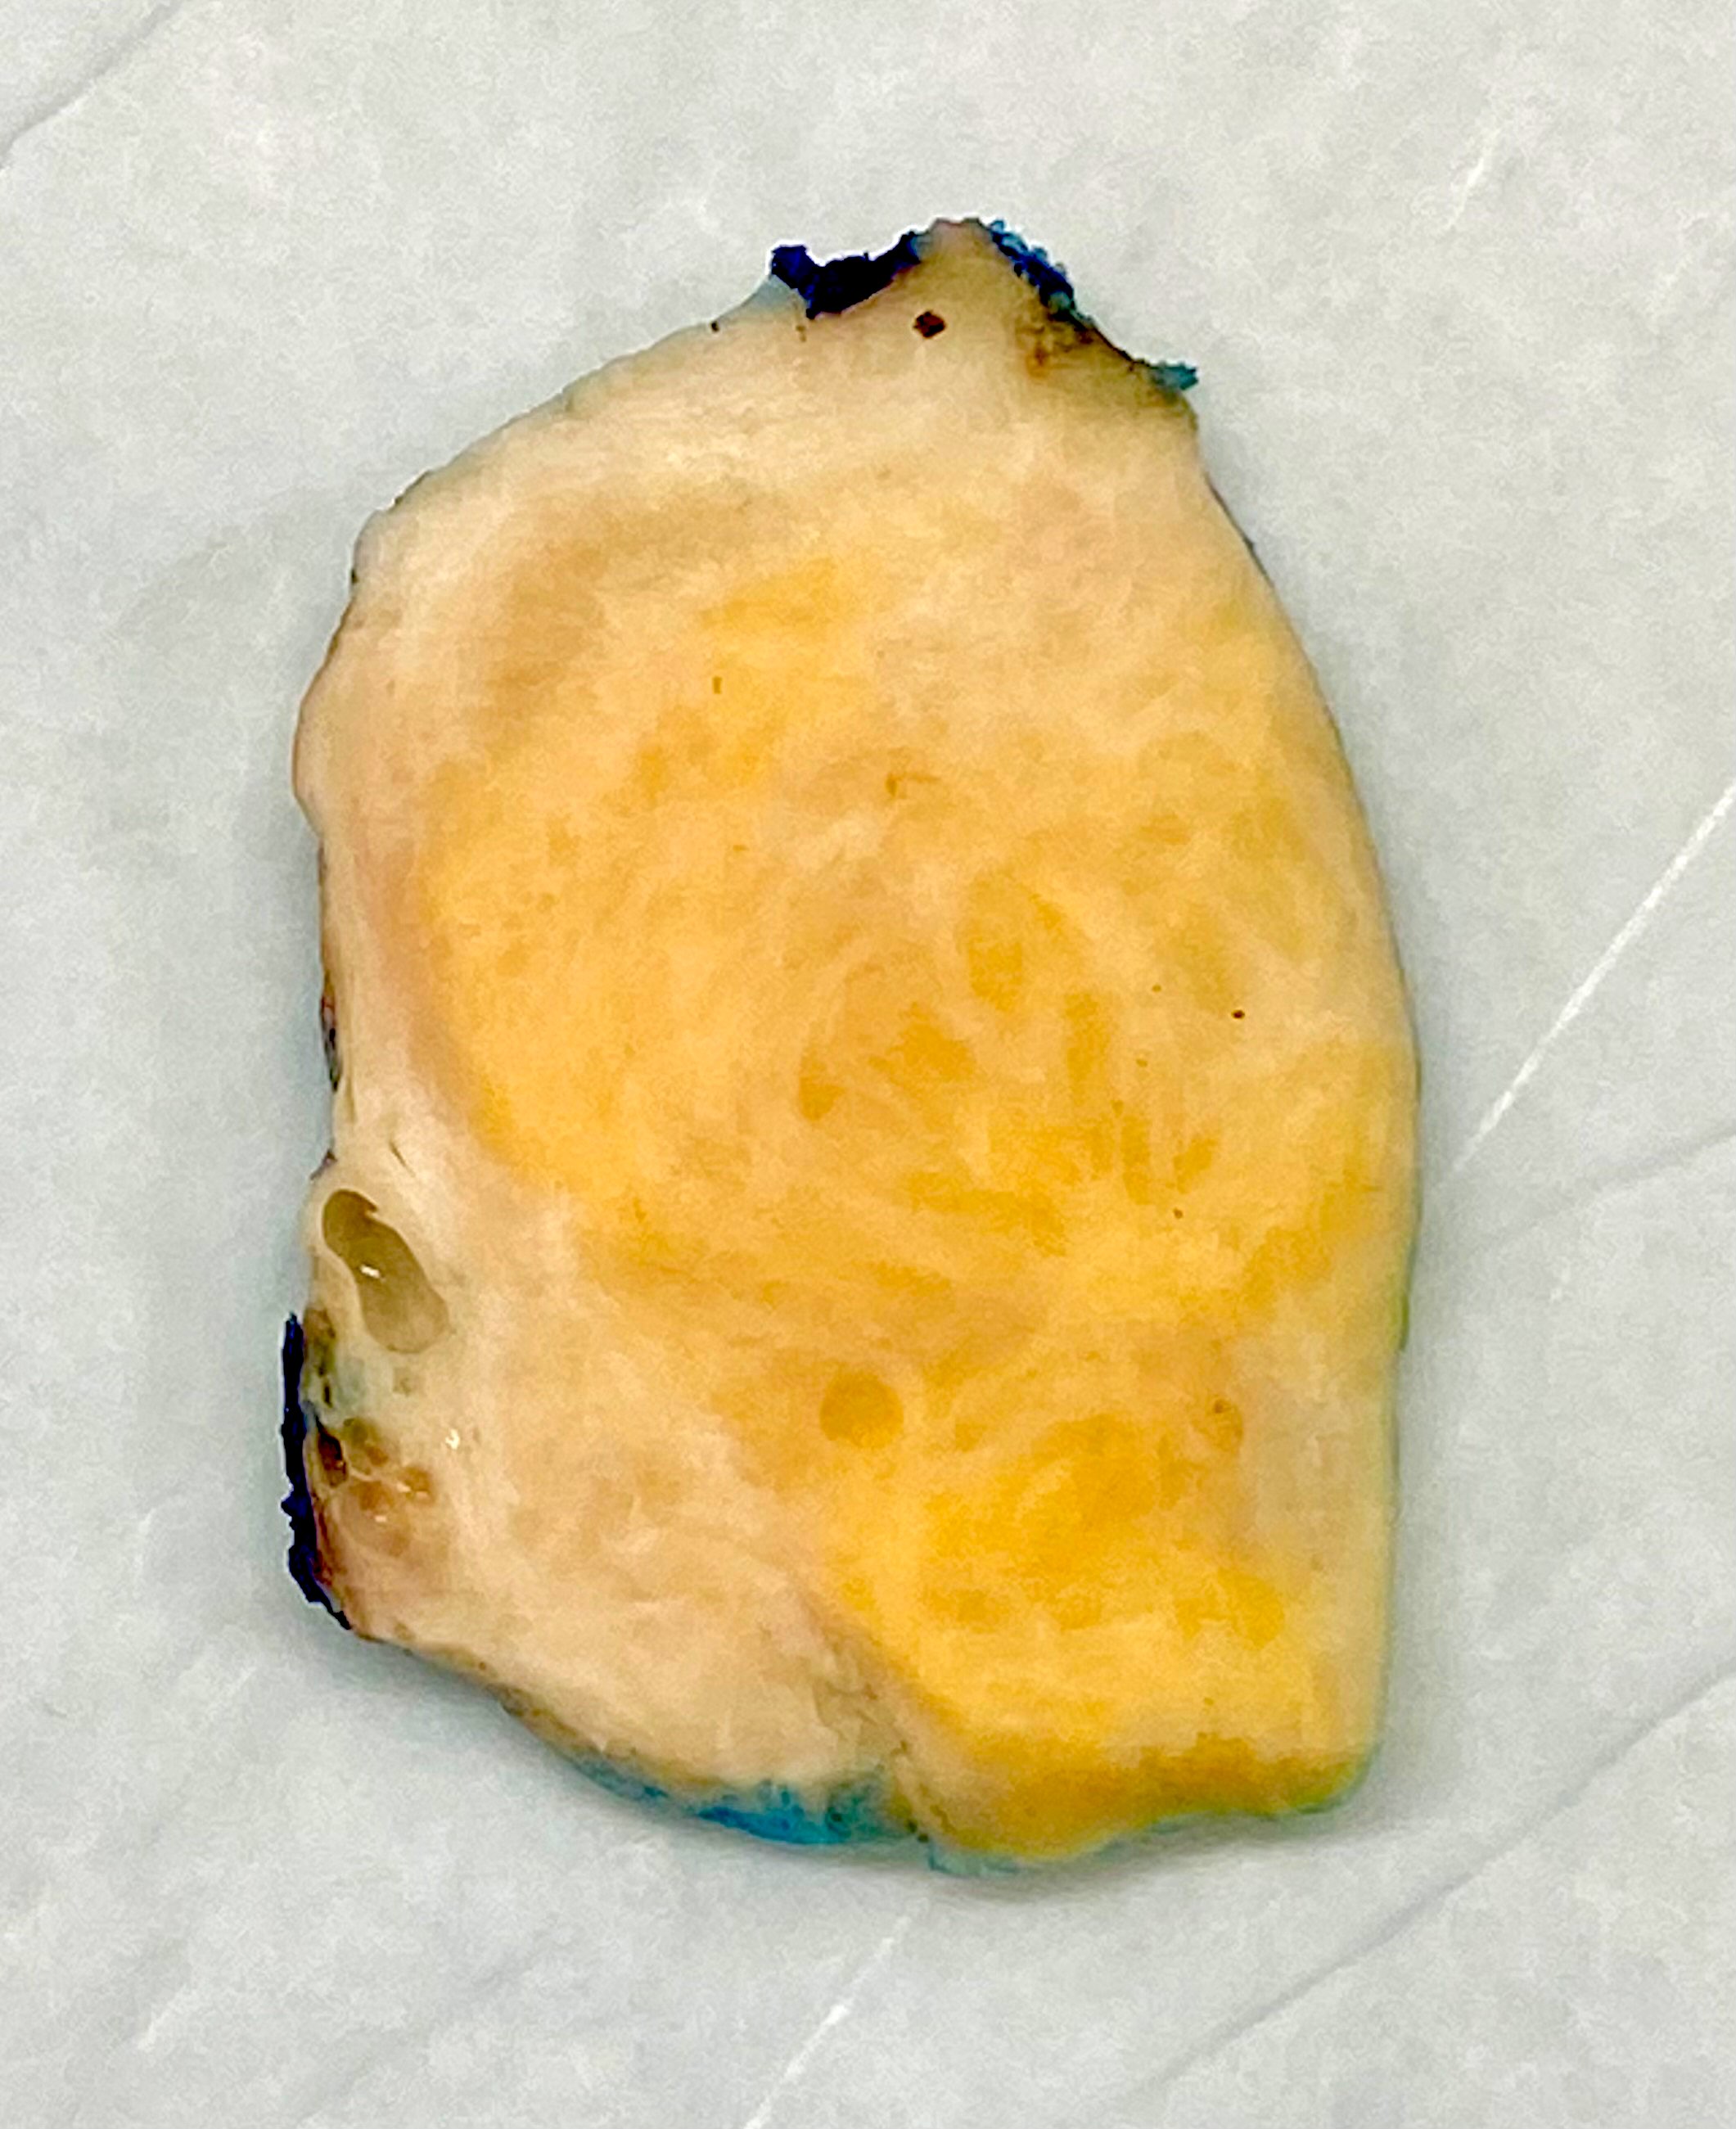

Gross description

- Usually unilateral

- Most are < 5 cm

- Solid, yellow and lobulated or white with focal yellow areas

- Occasionally cystic change and hemorrhage are present

- Necrosis is rare (Am J Surg Pathol 2014;38:1023)

Gross images